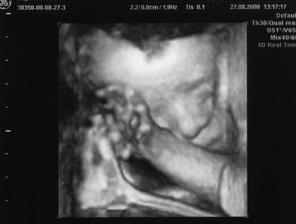

26.8.2008 ( 26.tt ) jsme jeli do Liberce na 4D utz,ale jelikož tam byl doktor,který tomu prd rozuměl a i záběry stáli za prd,tak jsem hned druhej den ráno volala,že jsem nespokojená a tak mi paní doktorka nabídla,at přijedu znovu a tak jsem s tchynkou nasedla na vlak a jeli jsme tedy 27.8.2008 a záběry máme opravdu krááásné a ty zážitky a vzpomínky 🙂 Prostě nááádhera,vím jistě,že jak budu podruhé těhotná,že tam pojedu znovu !!!